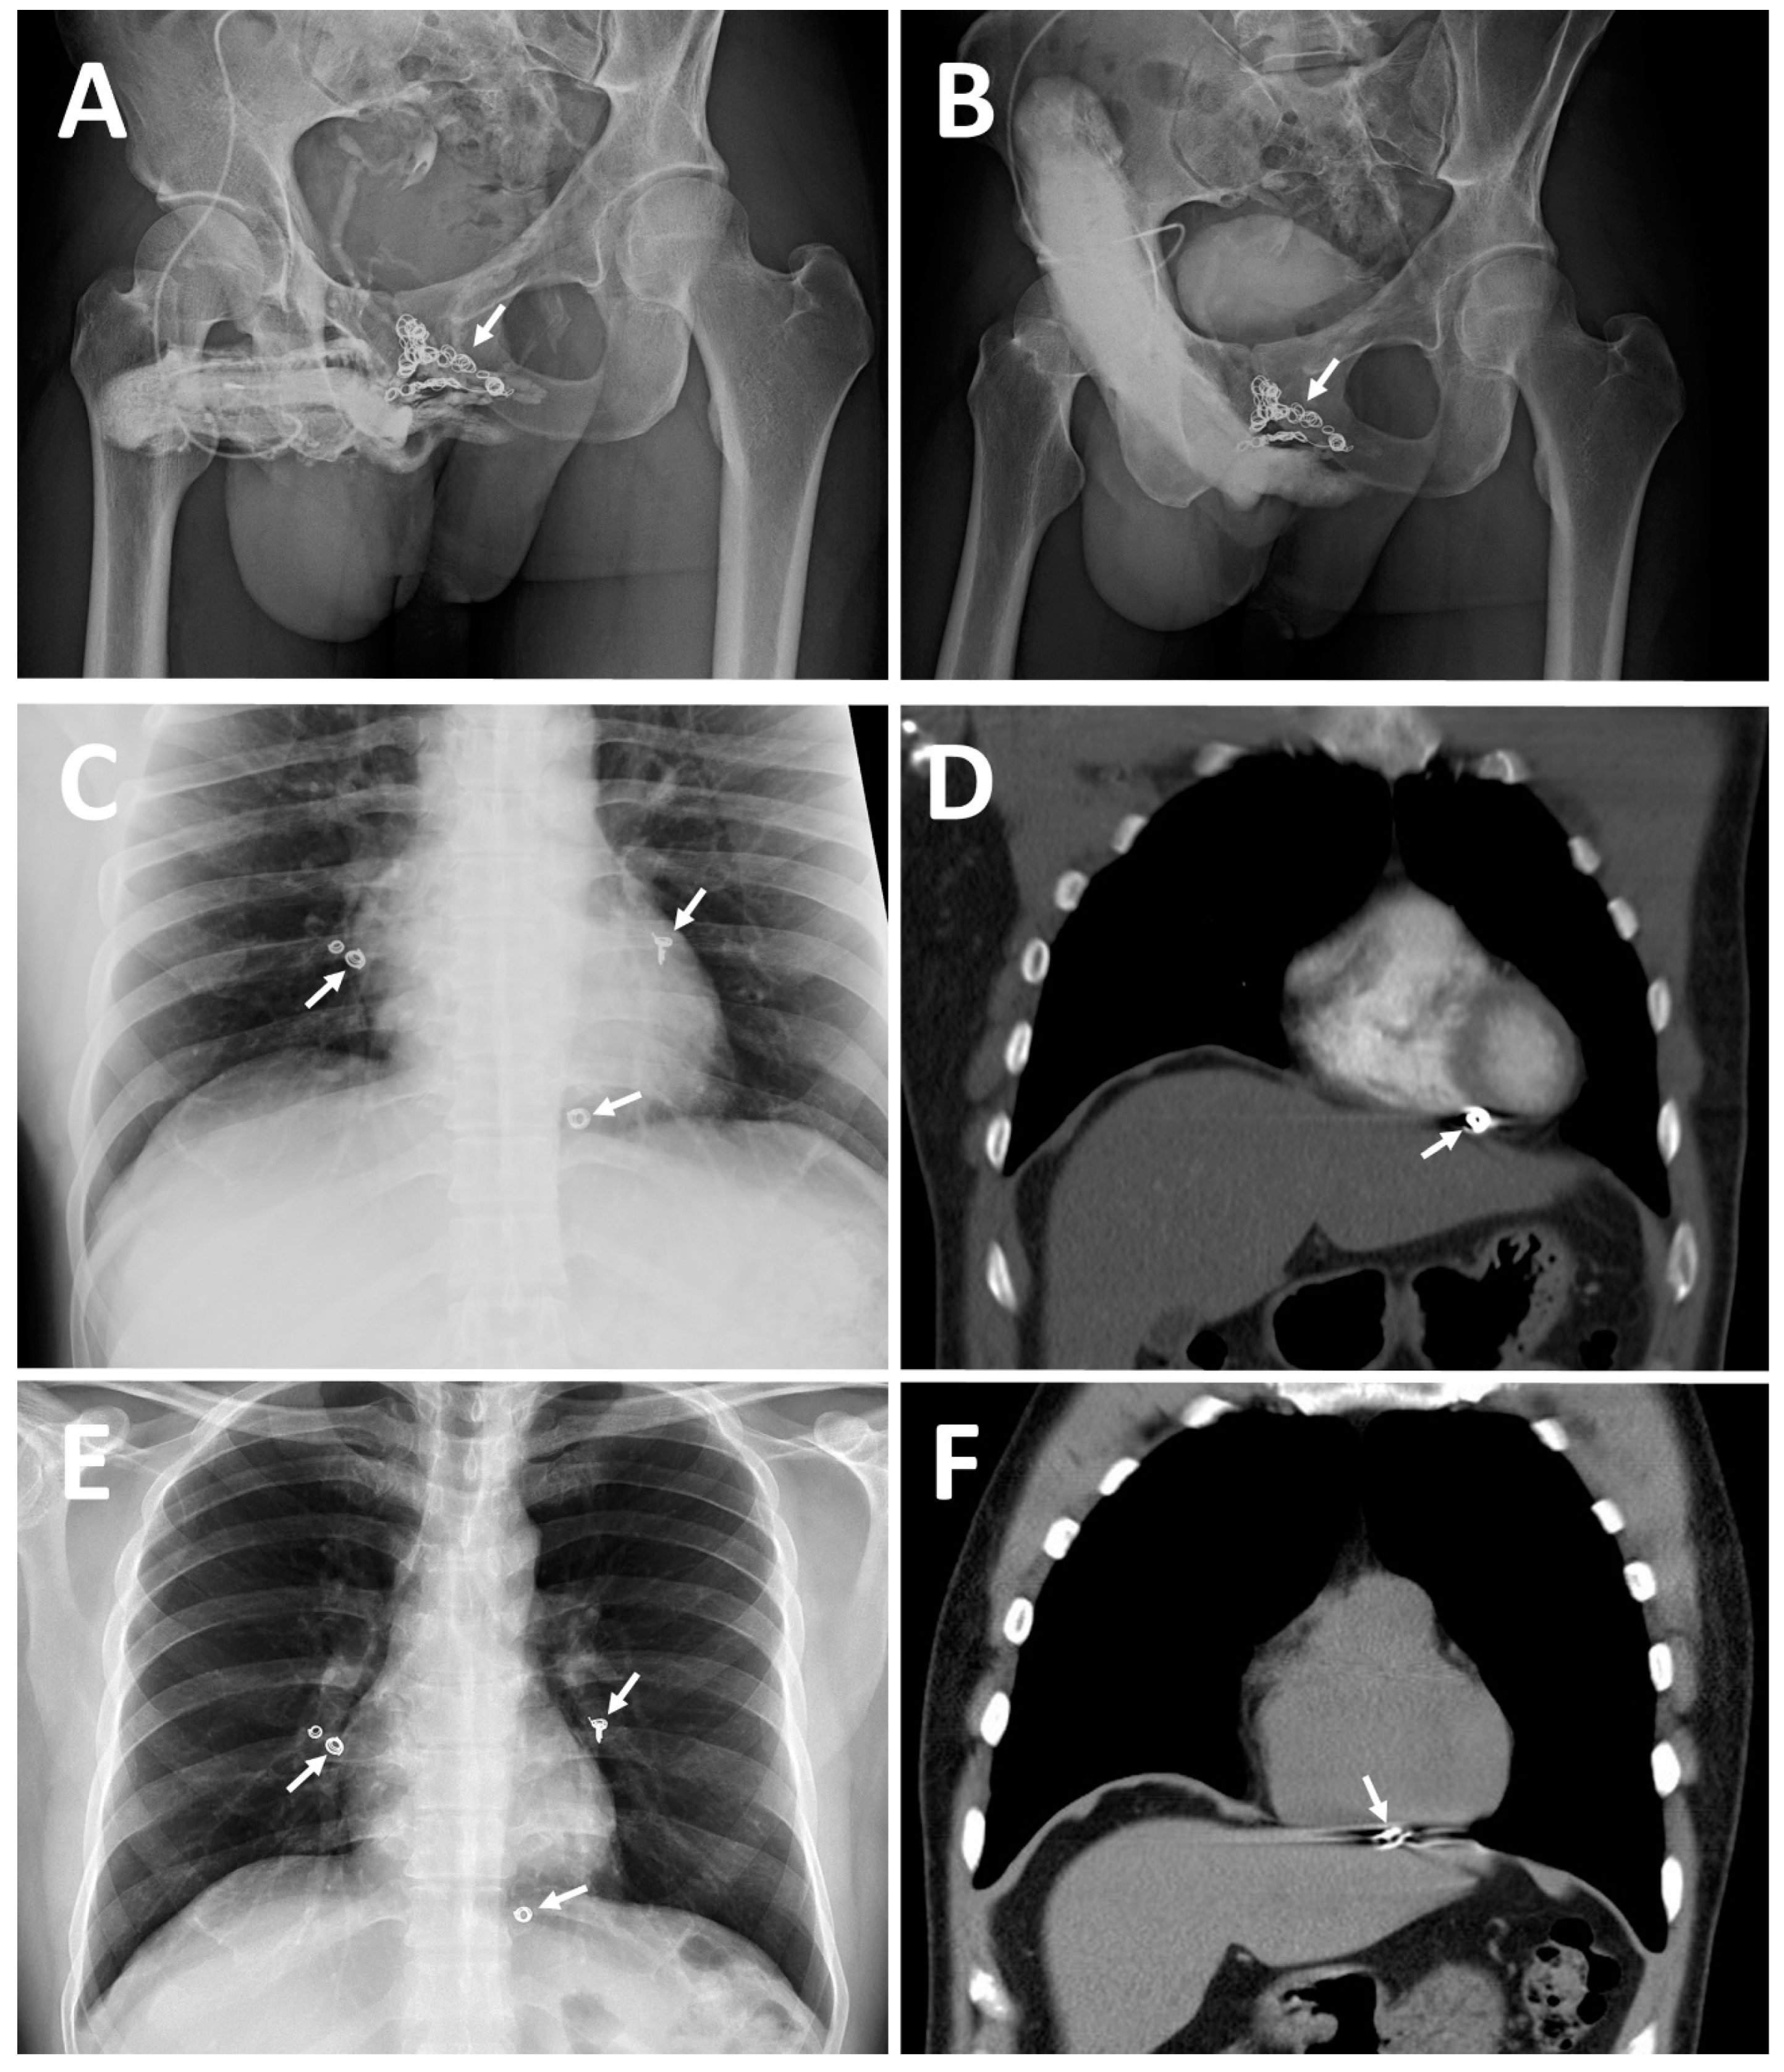

- Moriel, E.Z.; Mehringer, C.M.; Schwartz, M.; Rajfer, J. Pulmonary migration of coils inserted for treatment of erectile dysfunction caused by venous leakage. J. Urol. 1993, 149, 1316–1318. [Google Scholar] [CrossRef]

- Hsu, G.L.; Chang, Y.K.; Chiang, I.N.; Hsu, C.-Y.; Chang, H.-C.; Chueh, S.C.J. A case report of right cardiac ventricle perforation by uncontrolled embolization coil inserted for treating penile veno-occlusive dysfunction. Urol. Case Rep. 2022, 44, 102166. [Google Scholar] [CrossRef]

| CE(I) b | 2010 | Same | Acute chest pain was caused by the migration of a dumbbell-shaped coil to the right pulmonary artery. |